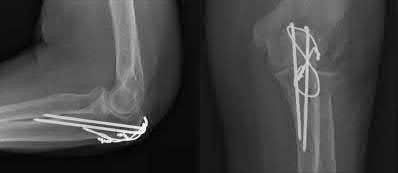

A 5-year-old boy falls from monkey bars and sustains a widely displaced supracondylar humerus fracture. Upon presentation to the emergency department, the hand is pink but the radial pulse is absent. He undergoes prompt closed reduction and percutaneous pinning. Post-operatively in the recovery room, the radial pulse remains absent, but the hand is warm with brisk capillary refill (less than 2 seconds) and normal oxygen saturation on the index finger. Which of the following is the most appropriate next step in management?

Correct Answer: Observation with close neurovascular monitoring

The patient has a 'pink, pulseless' hand following reduction and pinning of a supracondylar humerus fracture. Current pediatric orthopedic guidelines recommend observation for a well-perfused (pink, warm, brisk capillary refill) but pulseless hand post-reduction. The collateral circulation around the elbow is robust enough to maintain distal viability. Vascular exploration is indicated if the hand is white, cold, and poorly perfused (pulseless and ischemic) after a well-aligned reduction. Arteriography is generally not indicated and delays treatment if the limb is ischemic. Removing pins would destabilize the fracture and risk further neurovascular injury.